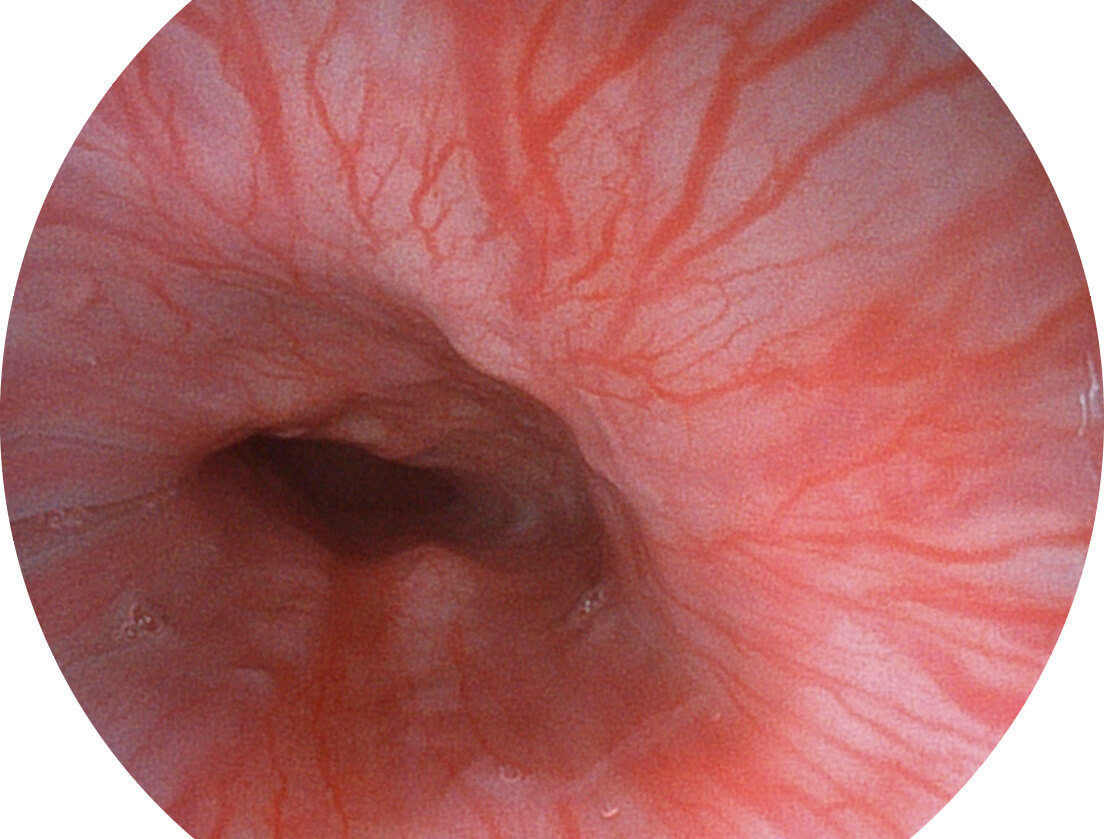

光电复合染色成像技术

Versatile Intelligent Staining Technology, VIST

强调浅层黏膜结构的同时,保证照明亮度和提升浅层微血管与中层血管颜色对比度,病变边界更清晰。

• 白光图像 VIST图像